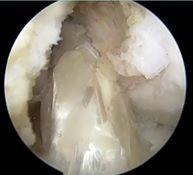

![]() | ![]() | ![]() |

| 大腿骨孔作成 | グラフト挿入 | 再建靱帯 |

バレーボールは膝関節に大きな負担が掛かり、特に回旋運動の制御が前十字靭帯の大きな役割になっています。競技者にとって前十字靭帯は必須であり、どうしても断裂してしまうと再建手術をしないと半月板損傷や軟骨損傷を引き起こし、その後、膝関節の破壊が進んでしまいます。今回はoutside in single rootでの再建手術を選択しました。術後は再建靭帯がきちんと機能し、半月板損傷や軟骨損傷を引き起こさず競技復帰が可能となりました。これからもバレーボールを頑張ってください。